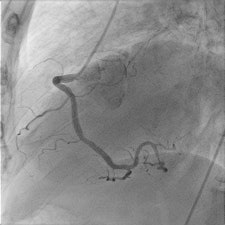

The main advantage for patients is a 50% reduction in total radiation dose through postprocessing of the images obtained by the flat-panel detectors. For one standard adult coronary angiogram, the typical dose used to be 6 to 7 mSv. Cardiologists at the Ghent lab are hoping they will be able to achieve 2 to 3 mSv.

"The quality and innovation of the four main cath lab companies -- Siemens, Phillips, GE, and Toshiba -- are very close, but in our case we chose the Phillips AlluraClarity system due to its radiation dose reduction capabilities," Taeymans said.